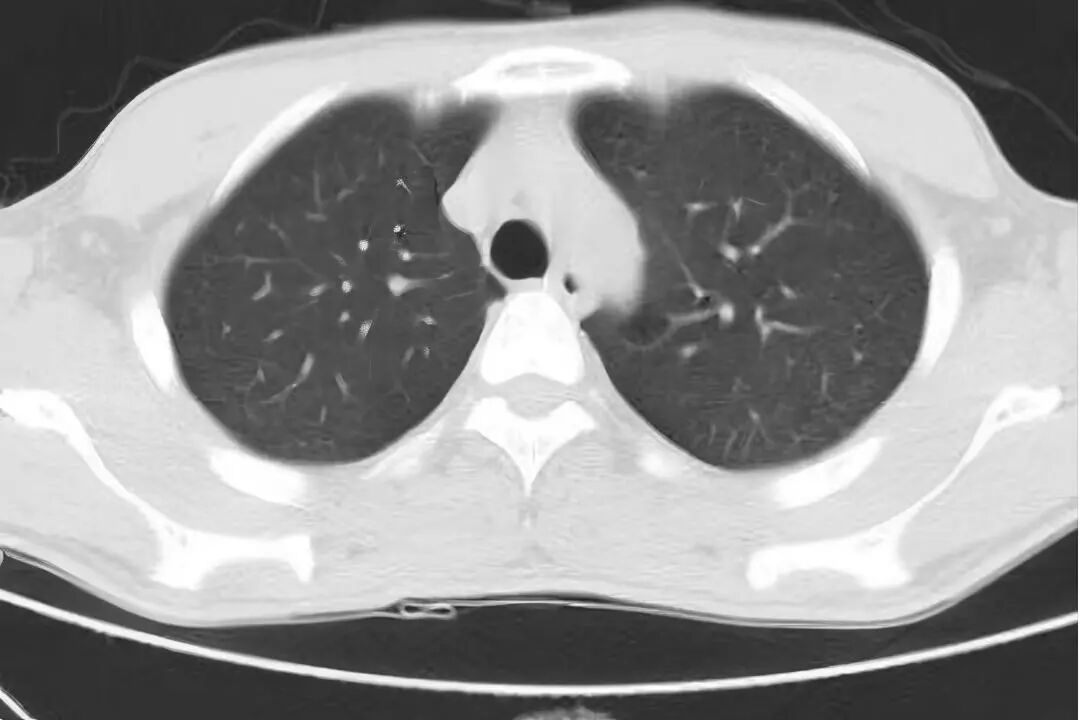

国庆假期期间,我院ICU成功救治一名罹患“罕见、危重、复杂”呼吸疾病的29岁患者。该患者因急性呼吸衰竭伴大咯血由外院紧急转入,入院时病情极为危重,胸部CT显示双肺弥漫性病灶,气管插管见大量血性液体,血氧饱和度一度降至50%以下。 入院时 CT提示双肺弥漫性病灶 近日复查 双肺渗出病灶明显吸收 入院时 肺部大量血性液体 住院期间 肺泡出血情况改善 接诊后,ICU团队迅速给予呼吸机支持、床旁支气管镜检查等救治措施,稳定患者生命体征。同时,医务部立即启动应急机制,组织呼吸与危重症医学科、肾脏风湿科、医学影像科、心血管内科、药学部等多学科专家会诊,国务院政府特殊津贴专家、呼吸与危重症医学科学科带头人廖江荣教授为患者进行床旁气管镜肺活检及支气管灌洗,诊断为弥漫性肺泡出血综合征(临床罕见、死亡率极高)合并急性呼吸窘迫综合征,为后续治疗提供了关键的循证依据。 ICU团队根据病情变化及时调整治疗措施,经过9天的精心治疗,患者生命体征保持平稳,肺泡出血情况逐步改善,肺部影像学表现明显好转,成功脱离了呼吸机支持,并转入普通病房继续治疗,现已好转出院。 专家提醒 弥漫性肺泡出血是以痰中带血、咯血、呼吸困难、进行性贫血和影像呈弥漫性肺泡浸润为特征的临床综合征。可由多种因素激发,基础疾病也多种多样,并且多数发病迅速,缺少特异性诊断方法,若不能早期诊断、及时治疗,则病死率很高。 若出现原因不明的急性呼吸困难、咳嗽、咯血等症状,特别是症状在短时间内迅速加重时,务必高度重视,应立即前往具备急救条件的医院就诊,争取早期诊断和治疗。 对于伴有自身免疫性疾病等相关基础疾病的患者,需定期随访,规范治疗,以预防严重并发症的发生。 贵州航天医院重症医学科专家简介 国务院政府特殊津贴专家 呼吸与危重症医学科 学科带头人 二级教授 硕士研究生导师 主任医师 学术任职: 亚洲冷冻治疗学会副主席 中国医药教育协会介入微创专业委员会呼吸分会副主任委员 中国防痨协会超声专业委员会副主任委员 中国抗癌协会肿瘤微创治疗专业委员会常务委员  中国防痨协会多学科诊疗专业委员会常务委员 中国医疗保健国际交流促进会结核病学分会常务委员 第一届中国人体健康科技促进会呼吸介入专业委员会常务委员 中国抗癌协会第一届肿瘤组织间植入治疗专业委员会常务委员 西部呼吸介入联盟副理事长 贵州省医学会呼吸病学分会第六届委员会副主任委员 贵州省中西医结合呼吸专业委员会副主任委员 贵州省医学会结核病分会常务委员 遵义市呼吸内科专业医疗质控中心主任委员 遵义市中西医结合学会理事长 专业擅长:  呼吸系统(肺)疑难病的诊断及危重病的抢救,呼吸系统(肺)感染性、疑难性疾病介入快速诊断(ROSE),尤其在肺癌、肺小结节早期诊断,肺癌微创综合靶向治疗,难治性、复治性、重症肺结核诊疗,硬质支气管下复杂性气道狭窄诊治,纤支镜介入治疗气道肿瘤、结核、气道狭窄(球囊扩张、支架植入、高频电刀、氩气刀、冷冻、灌洗、注药、微波消融),间质性肺疾病的诊疗上具有极高水平;带领团队勇于创新,在贵州省率先开展多项新技术、新疗法,如CT引导下及纤支镜下I125粒子植入及CT引导下微波、冷冻消融介入治疗肺癌等多项新技术,带动了贵州省肺部疾病的介入治疗水平提高。 刘东育 中共党员,重症医学科主任,主任医师 专业擅长:从事重症医学领域多年,擅长急危重症的各种抢救,有创呼吸机、无创呼吸机及CRRT的使用,对重症创伤及休克、急性重症胰腺炎、心脑血管疾病、各种急性中毒、多器官功能衰竭、重症肺炎及急性呼吸窘迫综合症等疾病的救治具有丰富的临床经验。 遵义市医学会重症医学分会第二届委员会常务委员,遵义市质量控制中心第一届重症医学质量控制中心委员会副主任,发表重症医学专业论文多篇,遵义市医学会第一届器官捐献与移植学分会常务委员。 赵洪伟 民建会员,重症医学科副主任,副主任医师 专业擅长:从事重症医学领域多年,擅长急危重症的各种抢救,有创呼吸机、CRRT的使用,对各种急性中毒、多器官功能衰竭、重症创伤及休克、心脑血管疾病、急性重症胰腺炎及急性呼吸窘迫综合症等疾病的救治具有丰富的临床经验。 贵州省重症医学委员会委员、遵义市重症医学会委员、遵义市医学会重症医学分会委员,贵州省第一批援沪医疗队队员,发表重症医学专业论文多篇。 王  磊 致公党党员,重症医学科副主任医师 专业擅长:从事重症医学多年,擅长急危重症的各种抢救,对急性重症胰腺炎、重症创伤及休克、急性呼吸窘迫综合症等疾病的救治、有创呼吸机的使用,CRRT对各种急性中毒、多器官功能衰竭、脓毒血症等疾病的救治具有丰富的临床经验。 贵州省重症医学委员会委员、遵义市重症医学分会委员、遵义市播州区方舱医院医疗队队员。 吴英武 中共党员,重症医学科副主任医师 专业擅长:擅长各种急危重症的抢救,对脓毒血症、重症创伤及休克、重症胰腺炎、急性呼吸窘迫综合症等疾病的救治及在重症超声对危重症治疗、抢救等方面具有丰富的临床经验。 贵州省第一批援鄂医疗队队员、贵州省重症医学委员会委员、遵义市医学会重症医学分会委员,发明专利3项、发表重症医学专业论文多篇。 贵州航天医院重症医学科简介 贵州航天医院重症医学科目前共有医护人员27人,其中副高级以上专家5人,开放床位16张,床单元配备医疗桥架和床旁监护系统,心电监护27台、动态血流监测仪23台、有创呼吸机19台、无创呼吸机5台、高流量呼吸机2台、转运呼吸机1台、血气分析仪1台、除颤仪1台、床旁透析机1台、纤支镜1台、无创血流动力学监测仪(USOM)1台、床旁B超机1台,降温毯1台、输液泵10台、微量注射泵74台、空气消毒机2台。 专科特色技术 心脏电转复及除颤术,气管插管术(经鼻气管插管术、经口气管插管术),气管切开术(经皮快速气管切开术、纤支镜引导下经皮快速气管切开术、超声定位纤支镜引导下经皮快速气管切开术),呼吸机的临床应用、心电、血压、脉搏、血氧饱和度监测技术、有创动态血压监测技术,有创动静脉置管术、锁骨下静脉穿刺技术、颈内静脉穿刺术、股静脉穿刺术、腋静脉穿刺置管术、血液净化临时血管通路的建立、鼻空肠置入术,跨肺压指导ARDS通气患者PEEP滴定应用,床旁超声测量视神经鞘直径评估颅内压,重症肺部超声评分在COPD患者中治疗效果应用,重症膈肌超声运动评估在机械通气患者撤机拔管中的应用,床旁超声测量下腔静脉呼吸变异指数在脓毒性休克机械通气患者容量反应性评估中应用价值。 诊疗范围 (一)急性、可逆、已经危及生命的脏器功能不全,经过严密监测和加强治疗短期内可能得到康复的患者。 (二)存在各种高危因素,具有潜在生命危险,经过严格监护和有效治疗可能减少死亡风险的患者。 (三)在慢性脏器功能不全的基础上,出现急性加重且已危及生命,经过严密监测和治疗可能恢复到原来状态的患者。 (四)其他适合在重症医学科进行严密监测和加强治疗的可逆性疾病患者 END